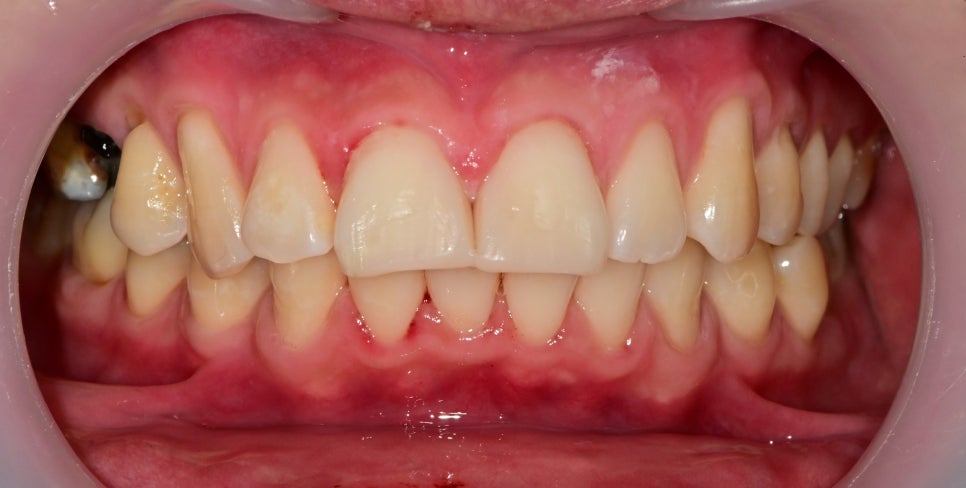

2주 후 체크를 했습니다.

고정 장치를 제거하고 치료 중간에 사진이긴 합니다만

치아의 흔들림은 이제 잡혔지만

가운데 고정했던 치아의 색이 어둡게 변한 것을 볼 수 있습니다.

일반적으로 치아의 신경 즉, 치수 괴사가 일어나게 되면 치아가 어두워집니다.

이것은 이미 생활력을 잃었기 때문에 해당치아는 신경치료 후 크라운치료를 결정했습니다. 그 옆의 치아 또한 파절편에 컸고 주변 금이 가있는 치아파절편들이 많지만 신경의 생활력은 살아있어서 신경치료 없이 크라운치료로 마무리하기로 했습니다.